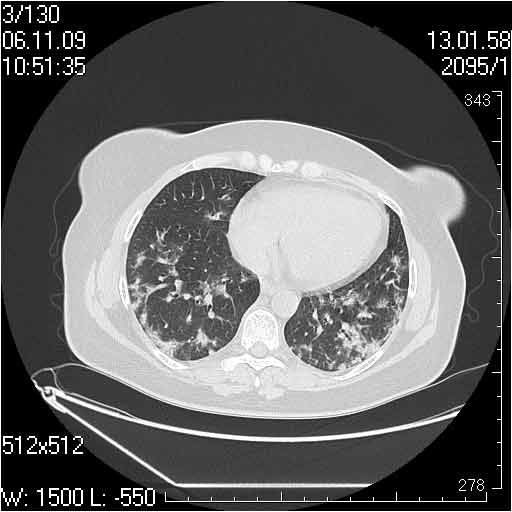

Случай №1

Женщина 50 лет.

Случай 1: изменения характерны для интерстициальной пневмонии (IIP/UIP idiopathic interstitial pneumonia/usual interstitial pneumonia); говорить о конкретной форме без открытой биопсии затруднительно.